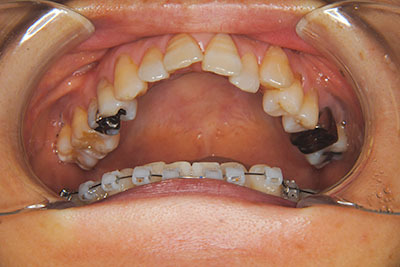

子供の頃に矯正治療を行う方が治療期間が短く済むというのは、確かですが、矯正治療は患者様の意識も重要です。

いくら歯が動き易くとも、本人がやる気でなければ効果は出ませんし、むし歯発生のリスクも高まります。おとなの方は顎の成長が終わっているため、治療の計画が立てやすいとも言えます。「もう大人だから…」とあきらめず、一度ご相談ください。